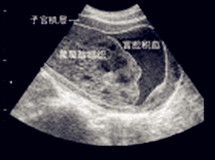

本病是婦產科常見病,其特點是月經的周期、經量發生嚴重紊亂。中醫認為本病的發病機理主要是沖任損傷,不能制約經血,故經血從胞宮非時妄行。臨床上大體分為血熱型、血虛型、脾虛型、血淤型、肝腎陽虛型等五型,辨證施治可收到良好效果。

子宮2、月經周期中有排卵,但排卵後孕激素分泌不足或過早衰退,導致排卵型功血。